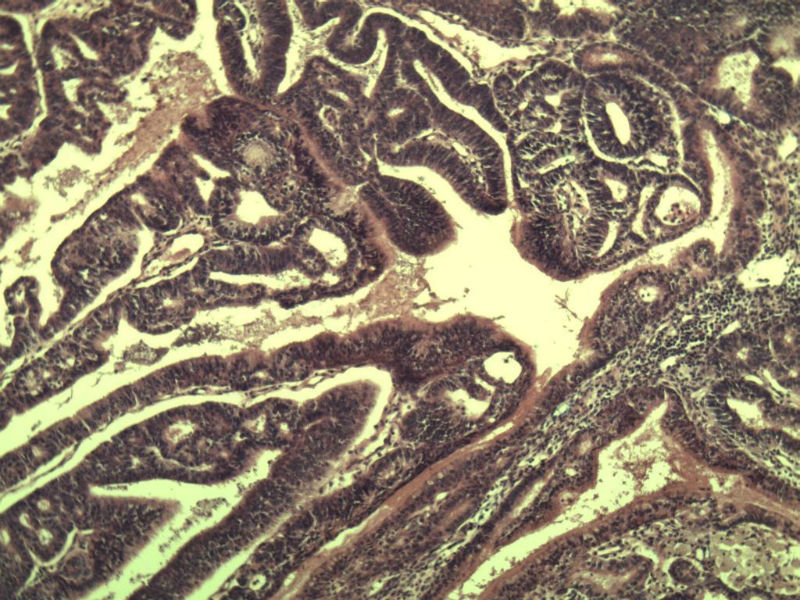

女 32岁 不规则阴道流血 一年  请各位老师看看 谢谢了

遵义医学院附属医院会诊结果    "复杂性增生伴非典型性 "

补充一下病史 病人10个月前因月经不规则行诊刮 诊断非典型性增生  上了曼月乐避孕环(好像是缓慢释放孕激素的那种),         都用激素治疗大半年了 还是这个样子 我还是觉得是癌  只有追踪一下以后病人的情况吧

高分化子宫内膜样癌

非典型复杂性子宫内膜增生,应了解雌孕激素情况。

子宫内膜复杂性非典型性增生,局灶区间质肉芽样(图5)及蜕膜样变,不够癌,建议临床查激素水平并追踪。

从照片看,没看到浸润的地方,我考虑是子宫内膜重度不典型增生。